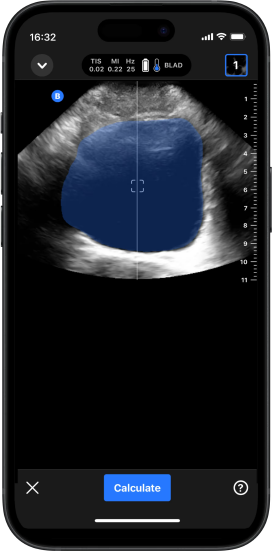

Bexiga Automática

Oferece cálculos automatizados do volume da bexiga, com visualizações 3D, em segundos. Simplifica a avaliação da retenção urinária para scanners menos experientes.